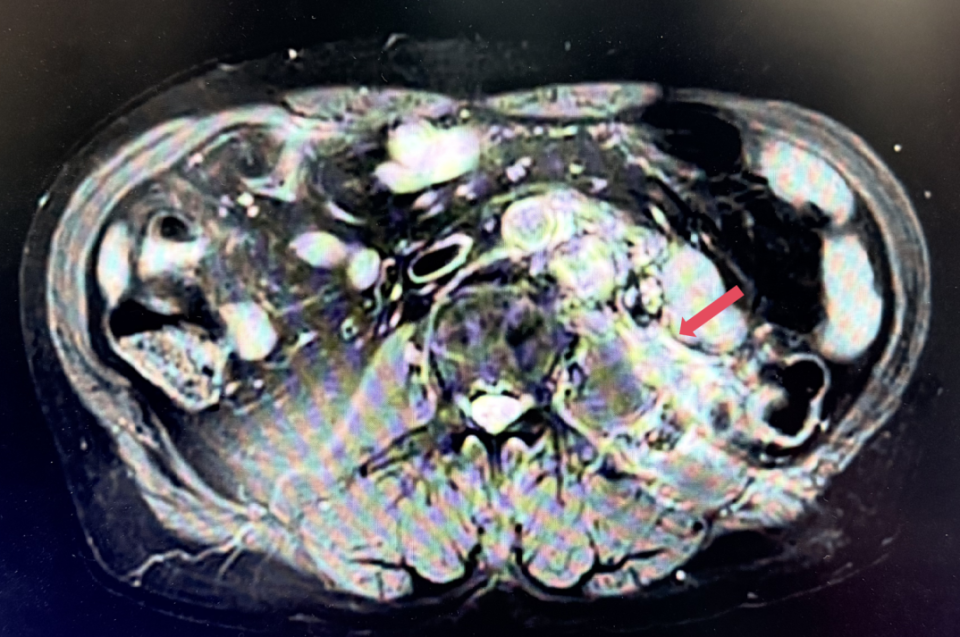

2023年11月,最深应答

2023年11月:治疗10个月(C15)评估,肿瘤负荷减少至41mm,维持PR。

患者初诊时68岁,2020年9月因“体检发现左肾占位2年”行腹腔镜下左肾根治性切除术,术后病理提示为肾透明细胞癌,pT3aN0M0,未行术后辅助治疗、未规律复查。2022年3月胸腹盆CT示腹膜后转移,IMDC评分0分,低危组。随后予一线培唑帕尼治疗,最佳疗效SD,2022年11月PD。于2023年1月经筛选进入Ⅲ期FRUSICA-2临床研究,开始接受呋喹替尼联合信迪利单抗二线治疗,用药6周(C2)后首次肿评即实现疗效PR(缩瘤率40.2%),用药10个月时缩瘤率近七成(68%),并维持上述水平至今,PFS已经超过37个月,在二线治疗中实现了长期无进展生存。同时,患者对呋喹替尼联合信迪利单抗方案耐受性良好,仅见轻微蛋白尿和偶然腹泻,未见其他不良反应,也未见免疫治疗相关不良反应。该方案有望为TKI经治的晚期肾癌患者带来新的选择,为实现长期生存提供可能性。